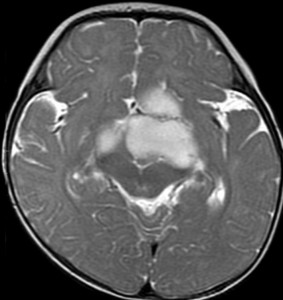

生後7カ月の幼児です。目が揺れるようになり(振り子様眼振)眼科を受診して腫瘍が発見されました。小児脳腫瘍の治療ができる病院へと紹介されました。

1ヶ月後にまたMRI検査がされました。乳児ですから検査にも麻酔が必要です。腫瘍は明らかに大きくなっています。左視神経から視索の腫瘍化が著しいので右側だけかすかに視力が残っているかもしれません。視力は明かりがわかる程度(明暗弁)と評価されました。